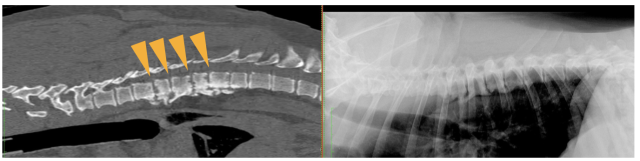

レントゲン検査では、椎間腔の狭小化(隣接する椎骨の隙間が狭くなること)・椎体の骨融解像(骨が溶けた状態)・椎体の硬化・骨棘形成などが認められます。【以下の画像参照】